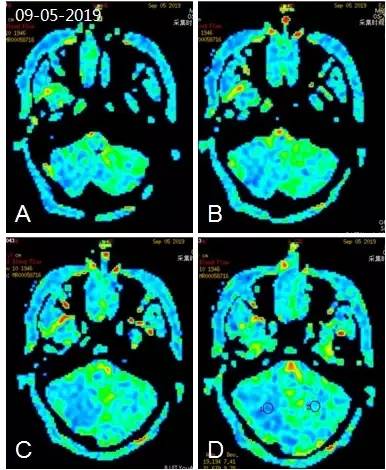

入院后头颅灌注核磁:双小脑半球脑血流值降低(图2)。

图2